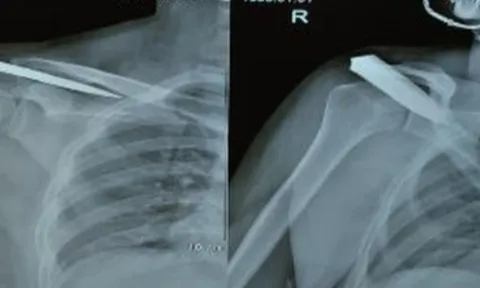

Mâu thuẫn gia đình, nam thanh niên bị đâm gãy dao

Nam bệnh nhân vào cấp cứu với lưỡi dao bị gãy, cắm sâu trong bả vai, gần vùng động mạch nguy hiểm đến tính mạng